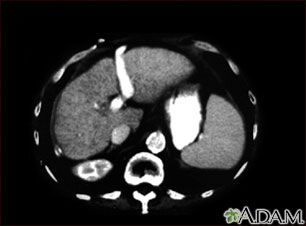

TC del abdomen superior mostrando cirrosis hepática.